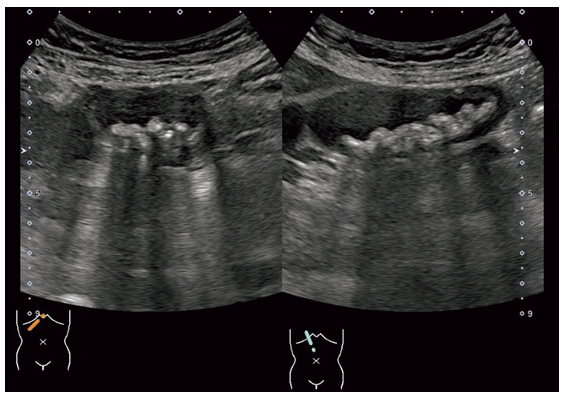

胆囊の超音波像を示す。

考えられる疾患はどれか。

胆嚢内に高エコーの丸い複数の固形物であることから、選択肢内から胆嚢結石と考えられる

答え 2